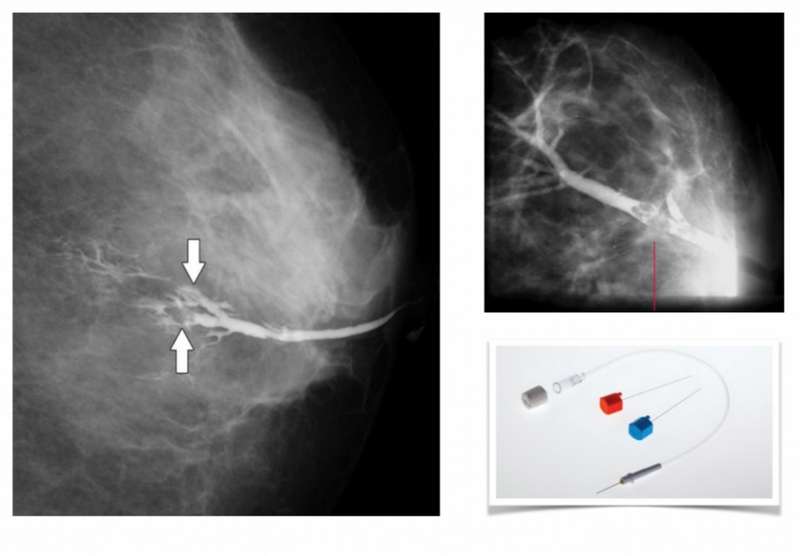

Дуктография – рентгеновское исследование молочной железы с введением контрастного вещества в протоки молочной железы. Разновидность маммографии. Применяется с целью диагностики внутрипротоковых новообразований (секреторная болезнь, облигатный предрак, рак).

Одной из эффективных диагностических методик по обнаружению патологий молочных желез является дуктография. Это рентгенографическое исследование, осуществляемое с помощью введения в протоки органа контрастного вещества. В результате на рентгеновских снимках четко визуализируются заполненные контрастом протоки, в просветах видны новообразования, воспалительные процессы. Процедура проводится с использованием специальной аппаратуры, обеспечивает высокий уровень точности и минимальную лучевую нагрузку.

• Врач обрабатывает сосок и вставляет в проток молочной железы расширитель и катетер. Через эту систему вводится контрастный препарат, позволяющий видеть состояние протоков.

• Как только препарат заполняет протоки - молочная железа помещается на маммограф, прижимается специальной пластиной. Производятся снимки в различных проекциях.